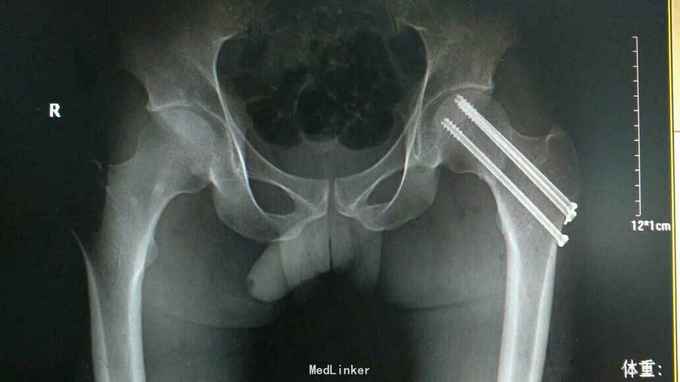

左股骨颈骨折 急诊手术,闭合复位空心钉内固定术

患者未出现,骨折愈合情况及股骨头坏死情况尚未得知。 讨论: 1.年轻人股骨颈文献显示有急诊手术的指证,早期复位固定可以减轻囊内压力,有利于血运重建,不知道大家有没有常规急诊手术? 2.为了减少坏死概率,也有不同的手术方式,如骨瓣植入,带血管腓骨移植等,不知道大家有什么好方法可以跟大家分享。